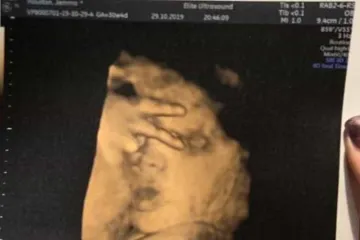

Իշխանություն առանց էթիկական կոդեքսի․ Վահան Իշխանյան Ռուս ուղղափառ եկեղեցին խզում է կապերը Հունաստանի ուղղափառ եկեղեցու հետ Գեղեցկության միջազգային մրցույթում Հնդկաստանի ներկայացուցիչը դարձել է «Միսս Կոսմո աշխարհ» Ֆրանսիայում Պակիստանի քաղաքացիներով բեռնատար են բռնել Ինչո՞ւ են «Երևանի» հայ ֆուտբոլիստները բոյկոտել գավաթային հանդիպումը Արցախի բանակի հրամանատարը նոր կոչումներ է շնորհել զորավարժությանն աչքի ընկած սպաներին Սաուդյան Արաբիայի արքայազնը «կանաչ լույս» է վառել երկրի պատմության խոշորագույն գործարքի համար «Լեւանտեն» պարտության մատնեց «Բարսելոնային» (տեսանյութ) 3 տարի շարունակ հետախուզվողին գտել են Համբուրգում ու տեղափոխել Երեւան Զիդան. Ռեալն A ու B կազմ չունի, ես բոլորի վրա հույս եմ դնում Իլոն Մասկը գովել է Ալեքսիս Օհանյանի Reddit ցանցը Հոլիվուդյան աստղ Ջեյն Ֆոնդան մի ամբողջ գիշեր է անցկացրել բանտում կլիմայական ակտիվիստների ակցիային մասնակցելու պատճառով «Բավարիայի» անսպասելի պարտությունը՝ 1։5, «Բորուսիաների» հաղթանակները Քանի՞ անվանակրգում Joker-ն «Օսկարի» կառաջադրվի «Ռոման» հաղթեց «Նապոլիին» առանց Մխիթարյանի Աֆղանստանում 8 երեխա է զոհվել դպրոցի մոտակայքում ռումբի պայթյունի հետեւանքով Գազիֆիկացվել է Նուբարաշեն վարչական շրջանի Բ թաղամասը Մոսկվայում և Մերձմոսկվայում եղանակային վտանգի «դեղին» մակարդակ է հայտարարվել Հայաստանի գավաթ. «Սևանն» ու «Վանը» դուրս եկան քառորդ եզրափակիչ Մալազիան Եվրոպային սպառնացել է ռուսական ինքնաթիռներ գնել Ղրղզստանի նախագահը հայտարարել է, որ պաշտոնավարման ավարտից հետո այլևս չի առաջադրվի Սիրիայում պայթյուն է որոտացել թուրքական բանակի վերհսկողության տակ գտնվող քաղաքում. 10 մարդ մահացել է Հոնկոնգում ցուցարարները հարձակում են գործել չինական Xinhua տեղեկատվական գործակալության վրա Սենատում քննարկվելու է Հայոց ցեղասպանությունը ճանաչող մեկ այլ բանաձեւ ԱՄՆ-ում 18-ամյա աշակերտը փորձել է քիլեր վարձել դպրոցի աշխատակիցներից մեկին սպանելու համար Սարատովում հայրը բռնել է տղամարդուն, որը փորձել է առեւանգել իր 10-ամյա աղջկան «Ուզում են ժողովրդին ահաբեկել». բնապահպանը` Ամուլսարի ճանապարհների ապաշրջափակելու մասին Դավիթ Տոնոյանը ՌԱԿ պատվիրակությանը ներկայացրել է բանակում լայնածավալ բարեփոխումների ընթացքը Ո՞վքեր են հայոց ցեղասպանության H. Res. 296 բանաձևի դեմ քվեարկած ԱՄՆ Ներկայացուցիչների պալատի 11 կոնգրեսականները 62-ամյա կինը միկրոավտոբուսում փող ու զարդեր էր գողացել. ոստիկանության բացահայտումը Գագիկ Խաչատրյանին մեղսագրվող արարքների հետևանքով ավելի քան 7 մլրդ 3 միլիոն դրամի վնաս է հասցվել. ԱԱԾ «Դուխով» նստարաննե՞րն էլ է Սերժ Սարգսյանինը եղել Արարատ Միրզոյանն ընտրվել է ԱԺ նախագահ՝ լինելով ՀՀ առաջին փոխվարչապետի պաշտոնակատար Քոչարյանի ազատման համար հարթակ է ստեղծվել Դեռ չծնված երեխան ուլտրաձայնային հետազոտության ժամանակ հաղթանակի՝ «V» նշանն է ցույց տվել՝ ապշեցնելով բժիշկներին Ո՞նց կարար Գեւորգ Կոստանյանը ինձ գար ասեր` այս թուղթը փոխի Լարվածությունը համեմատաբար ակտիվ էր. Դավիթ Բաբայանը՝ սահմանային իրավիճակի մասին Ֆրանսիային է մոտենում «Ամելի» փոթորիկը Մարտաֆիլմ հիշեցնող սպանություն Նորատուսում. 20-ից ավելի կրակոցից կա 1 զոհ, 1 վիրավոր.վարկածներից մեկը վենդետան է Վերջին տուրում Հայաստանի հավաքականը հաղթանակ տարավ Սուրճը, գազավորված ըմպելիքները, արմավենու յուղը. ո՞ր մթերքներն են կալցիումը դուրս բերում օրգանիզմից Անպատասխանատու քայլ է «Ռազմագիտությունը» դպրոցական ծրագրից հանելը․ ռազմական փորձագետ Հանրապետության թիվ 1 առանձնատան մասին. Նիկոլ Փաշինյանը ուղիղ եթերում է Գագիկ Հարությունյանը շարունակո՞ւմ է լինել ՍԴ նախագահ․ փաստաբան (տեսանյութ) Ռոնալդուի մայր. Ֆուտբոլային մաֆիան չի թողնում, որպեսզի Կրիշտիանուն «Ոսկե գնդակ» նվաճի Մենք փորձում էինք բացատրել Չիկագոյին, որ դա հայրիկն է, բայց նա չէր հասկանում. Քիմ Քարդաշյանը լուսանկարներ է հրապարակել Հայաստանից գնացած քրգործերի մեծ մասը կփլվի ՄԻԵԴ-ում. Չալաբյան Թրամփը հայտնել է ներքին անվտանգության նոր նախարարի անունը Սնոուդենը պատմել է՝ ինչու չի շփվում ռուսական մամուլի հետ Եղանակը Հայաստանում. այս գիշեր Երեւանում եւս կլինի 0-ից ցածր